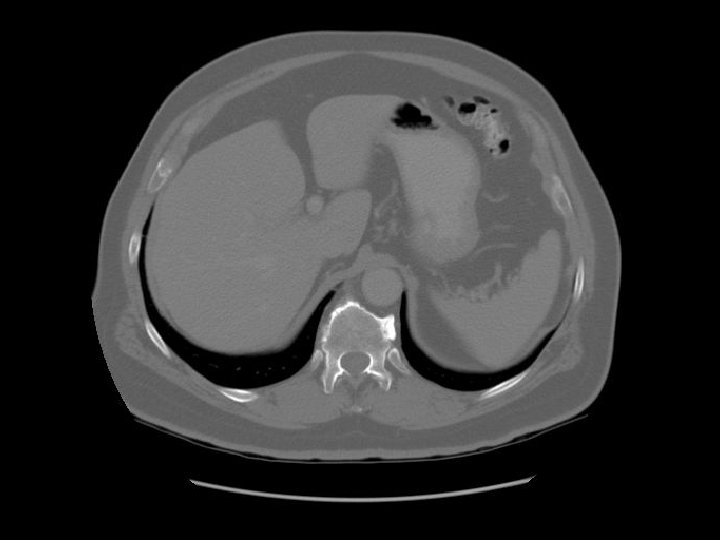

Stomach Liver Spleen

Lt lobe Rt lobe

Fissure for ligamentum teres Fissure for ligamentum venosum

Caudate lobe Diaphragm

Portal vein

Lt adrenal

Portal vein Rt adrenal

Surgical clips in gallbladder fossa.

Coeliac trunk

Pancreas Splenic vein The splenic vein lies in the posterior pancreatic grove and joins the superior mesenteric vein to form the portal vein.